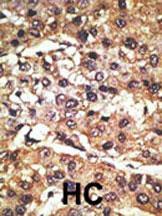

Supportive validation

- Submitted by

- Abcepta (provider)

- Main image

- Experimental details

- "Formalin-fixed and paraffin-embedded human cancer tissue reacted with the primary antibody, which was peroxidase-conjugated to the secondary antibody, followed by DAB staining. This data demonstrates the use of this antibody for immunohistochemistry; clinical relevance has not been evaluated. BC = breast carcinoma; HC = hepatocarcinoma."

- Primary Ab dilution

- 1:50~100